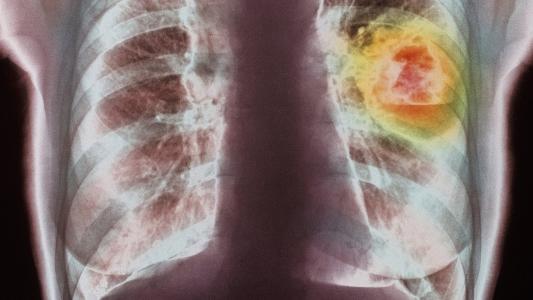

基因靶向药物与晚期肺癌之间的战争

新的临床试验发现,两种靶向遗传缺陷的药物,正在给予具有特定类型晚期肺癌患者生存期更长,提高生活质量的新希望!

艾乐替尼

来自新的全球临床试验表明,新批准的名为“艾乐替尼”(Alecensa)的药物,目前用于ALK-阳性非小细胞肺癌患者,有效时间是标准药物的两倍。美国癌症协会(ACS)介绍,ALK是一种可以产生有助于癌细胞生长和传播的蛋白质的基因,这类基因驱动的肺癌形式在非吸烟者中更常见。

在另一项研究中,一种名为dacomitinib的实验药物可将具有(EGFR)突变的非小细胞肺癌患者生存期延长约一半。 这种突变在非小细胞肺癌患者中常见。EGFR是细胞表面帮助生长和分裂的物质。